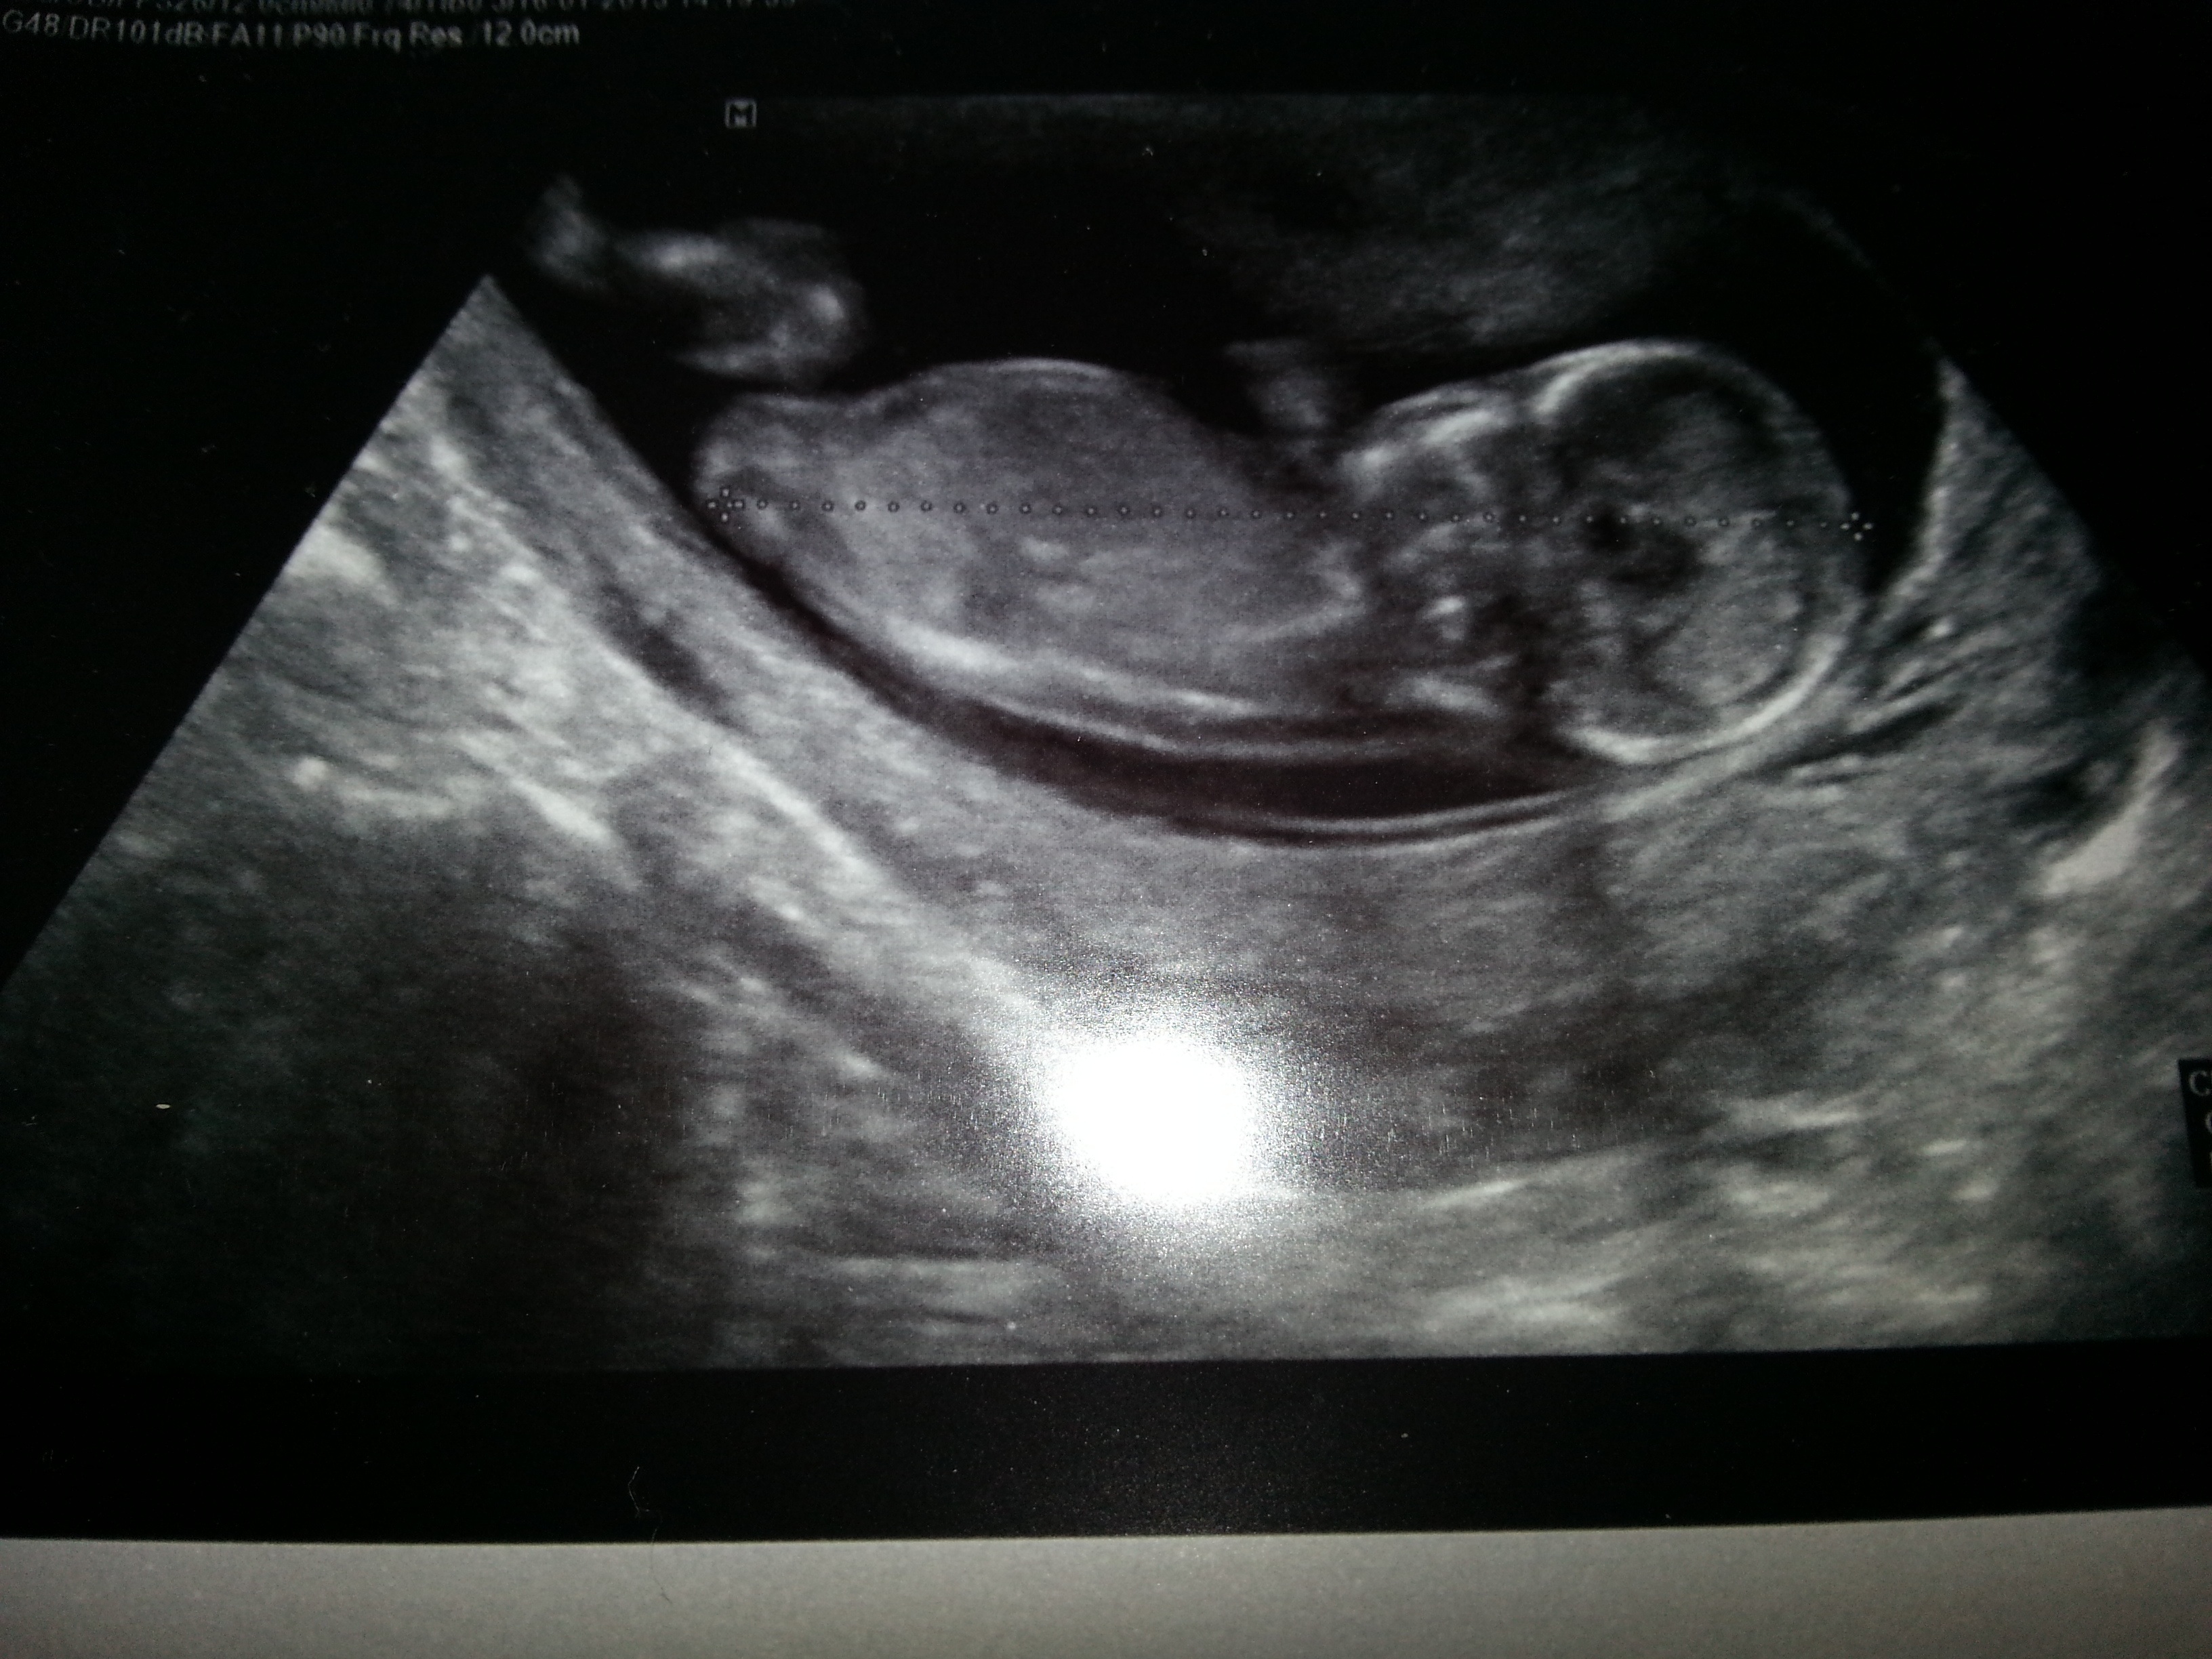

13 week scan.. Based on the skull theory, what do you think?? boy or girl? :):):):)Attachment 8590